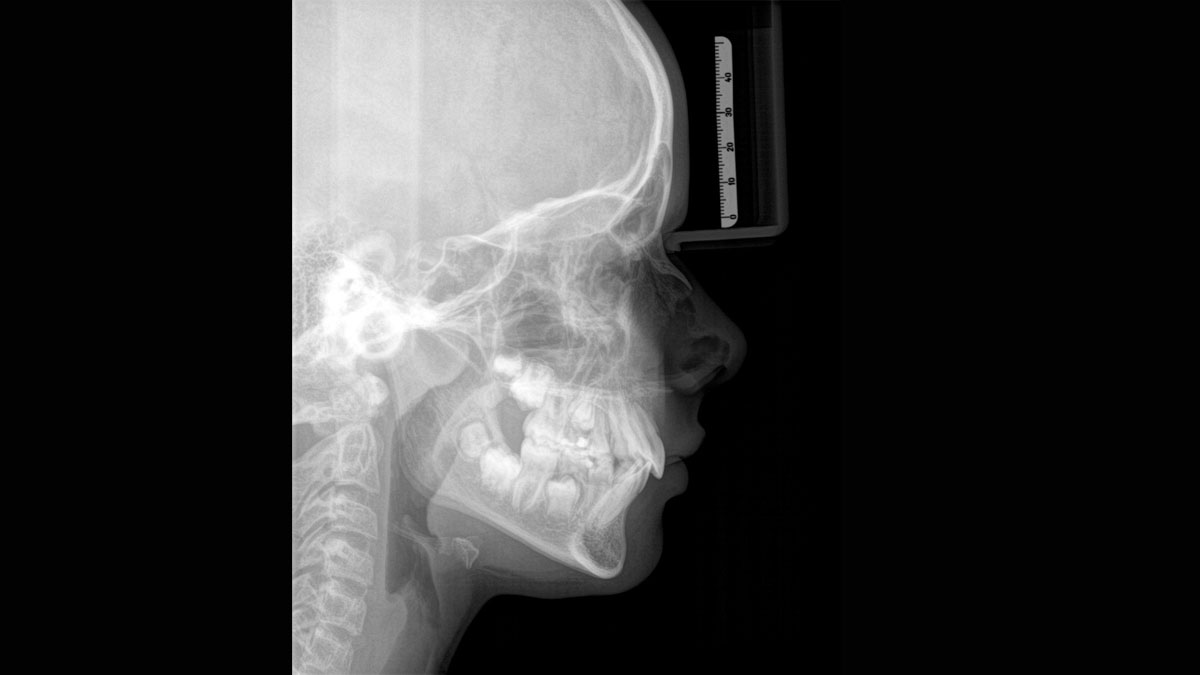

Für außergewöhnliche Panoramabilder mit hoher Schärfe. Sie können einen optionalen rechten oder linken Fernröntgenausleger wählen, der jederzeit nachgerüstet werden kann.

Dank des optimierten Low Dose Modus mit dediziertem Filter wird die Abbildung dichter Strukturen wie etwa Knochen bei stark reduzierter Dosis ermöglicht. Das macht Intelligent Low Dose zu einer attraktiven und effizienten Option bei vielen klinischen Fällen. Ob in der Kieferorthopädie oder Implantologie – mit den Dentsply Sirona Lösungen finden Sie für jeden Fall die optimale Einstellung.